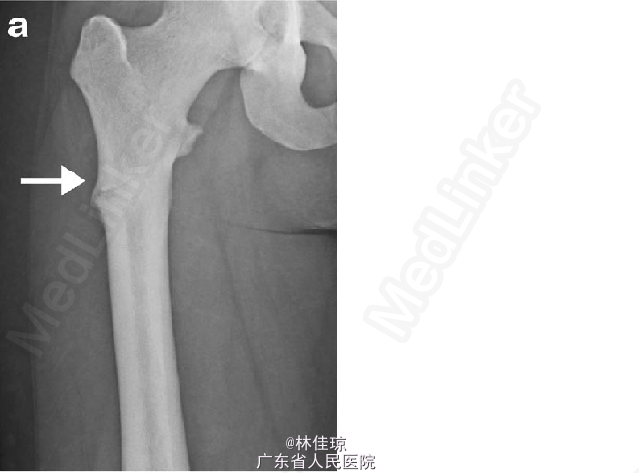

体格检查:颅面畸形、小颌畸形、手部短宽、身材矮小。腹部大小与妊娠周数相符,左下肢明显缩短、外旋畸形,皮肤完整,神经血管功能检查正常。 X 线提示股骨干横向骨折、皮质增厚,对侧股骨皮质增厚和外侧骨裂,提示可能发生骨折。

致密性成骨不全症合并股骨骨折 产科会诊后决定实施骨折切开复位内固定术,即:左侧股骨切开复位、髓内钉固定。术后 2 个月,患者分娩。分娩 2 周后双侧胫腓骨 X 线可见皮质增厚,另见胼胝体形成,与正常相比稍微减少,考虑到是不典型愈合,这与其破骨细胞功能紊乱相一致。手术 3 个月,患者左侧股骨疼痛明显减轻,但右侧股骨疼痛加重。X 线检查为右侧转子下不典型骨折。提议进行预防性手术,但患者本人拒绝。大约一周后,患者因跌倒后右侧下肢疼痛加剧就诊。X 线检查未见股骨进一步损伤。患者选择进行预防性固定术。